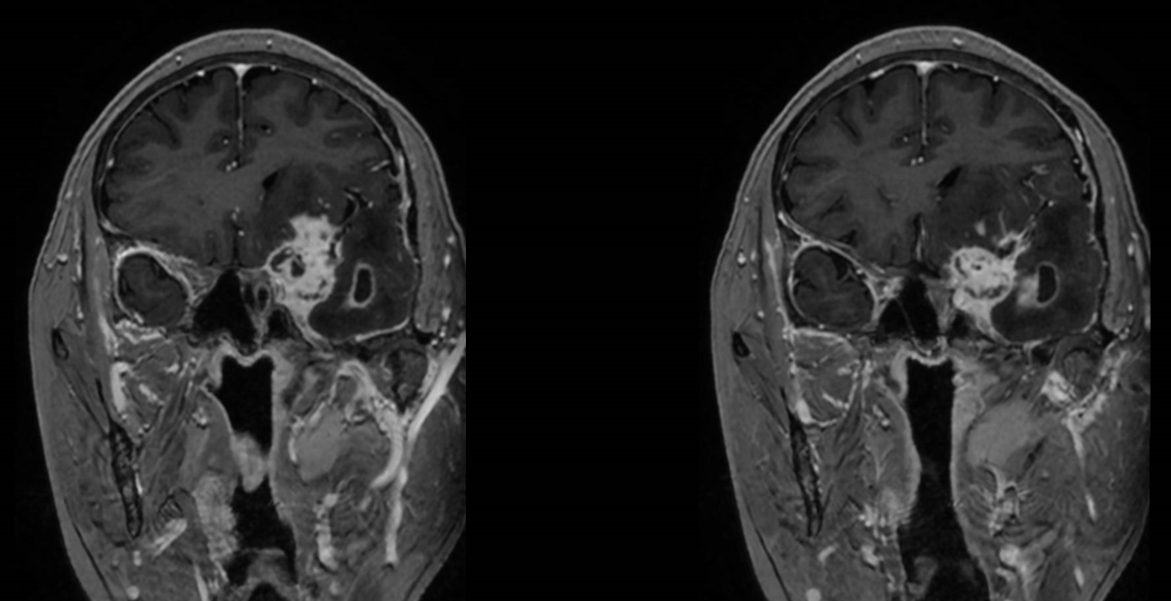

该患者入院后完善常规颅脑影像学检查,左侧颞叶病变,疾病性质不详,转移瘤、胶质瘤、炎症类疾病均不能排除,遂行PET-CT检查,提示左侧颞叶高代谢,淋巴瘤不能排除。组织MDT会诊建议可先行腰椎穿刺查脑脊液脱落细胞学、感染指标,若仍不能确诊,可进一步行开颅病灶切除,术中快速冰冻,根据冰冻结果决定手术手术策略。患者脑脊液脱落细胞学结果:较多淋巴细胞,少许单核细胞及个别中性粒细胞,未见异形细胞,脑脊液常规、生化、脑脊液培养未见细菌生长,诊断仍不能明确,且患者病情进展迅速,患者神志呈昏睡状态,颅脑MRI提示病变较前明显增大(影像学检查间隔两周),且水肿明显加重,遂行开颅病变切除术。术中见部分病变累及蝶骨嵴硬膜,病变质地硬韧,内有多个囊腔,囊内容物为黄色粘稠样脓性物质,留取囊液及实性部分送快速冰冻,在等待冰冻过程中,进一步探查见肿瘤侵犯左侧颞叶,该部位肿瘤质地相对软,无包膜,与周围脑组织无边界,血运不丰富,内有多个囊腔,且肿瘤侵犯侧裂池、颈动脉池,左侧视神经、颈内动脉、大脑中动脉均被病变包绕,且该处肿瘤质地偏硬韧。术中快速冰冻提示组织大片变性坏死,伴胶质增生及淋巴增生。结合病变质地及冰冻结果,考虑为非肿瘤性疾病,可能为炎性病变伴肉芽肿形成可能性大,且肿瘤质地硬韧,累及范围广泛,难以全切,遂行肿瘤大部分切除后结束手术。术后病理结果明确后予以伏立康唑、醋酸卡泊芬净抗真菌治疗。在治疗过程中患者先后出现脑出血、脑梗塞,最终因治疗周期长,花费高、效果不确定等因素,家属放弃治疗,于术后1月去世。